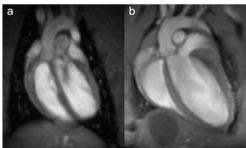

Fig. 1: Rat and mouse heart MRI. 4-chamber-views of a rat (a), upper panel and mouse heart (b), lower panel are displayed. Beside the lumen of the left and right chamber, the left and right atria, the myocardium and the up-going vessels are visible. For rat a 72 mm volume transmit-only together with 20 mm recieve-only planar surface coil, both room temperature, and for mouse the 72 mm volume transmit-only and the cryogenic 4 element 1H array receive-only coil were used. Intragate Flash (Fast Low Angle Shot) sequence for rat (repetition time: 6.2 ms; echo time: 1.3 ms; oversampling:150; flip angle: 10 deg; slice thickness: 1.0 mm; FOV: 45x45 mm and matrix: 128x128 .Intragate UTE (Ultra Short Echo Time) for mouse: repetition time: 8.0 ms; echo time: 0.36 ms; oversampling: 100; flip angle: 15 deg; slice thickness: 1.0 mm; FOV: 22x22 mm and matrix: 128x128.

MRI is a well-established modality for imaging of the cardiovascular system in rat and mice. Beside determination of tissue, organ or tumor sizes, our main focus lies on monitoring changes over time after treatment of transgenic mice. One of the best-known forms of dynamic MRI experiments is the functional MRI, typically monitoring changes in blood flow. In the recent years MRI has become the standard for the quantitative evaluation of cardiac function, masses, and infarct size. Wall motion and strain analysis are used to display myocardial dysfunction. To obtain information on the morphology and functional parameters of rat and transgenic mice heart, we established standard protocols that enable us to rapidly acquire high quality images.